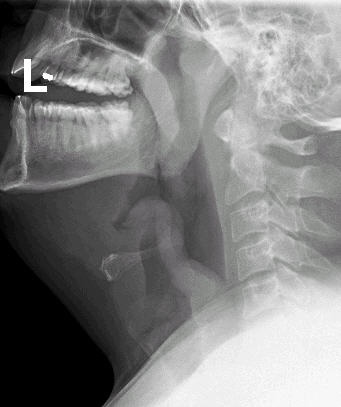

Filme lateral do pescoço demonstrando epiglotite

Do acervo pessoal de Dr. Petri; uso autorizado